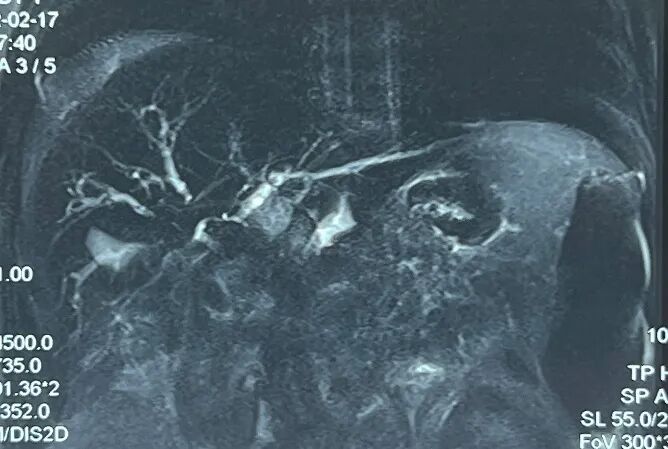

上腹增强MRI+MRCP:左肾癌术后,左肾缺如,肝门部后腹膜肿块,肝脏外缘、左侧腰大肌、腰髂肋肌及左侧腹部肌肉组织内多发异常信号,考虑多发转移灶。右侧膈下、腹腔及后腹膜多发转移灶及肿大淋巴结,门静脉主干受压、管壁毛糙。肝门胆管梗阻伴肝内胆管扩张。

MRCP:肝门胆管梗阻,其近端肝内胆管扩张,右前、右后及左侧肝内胆管互不交通。